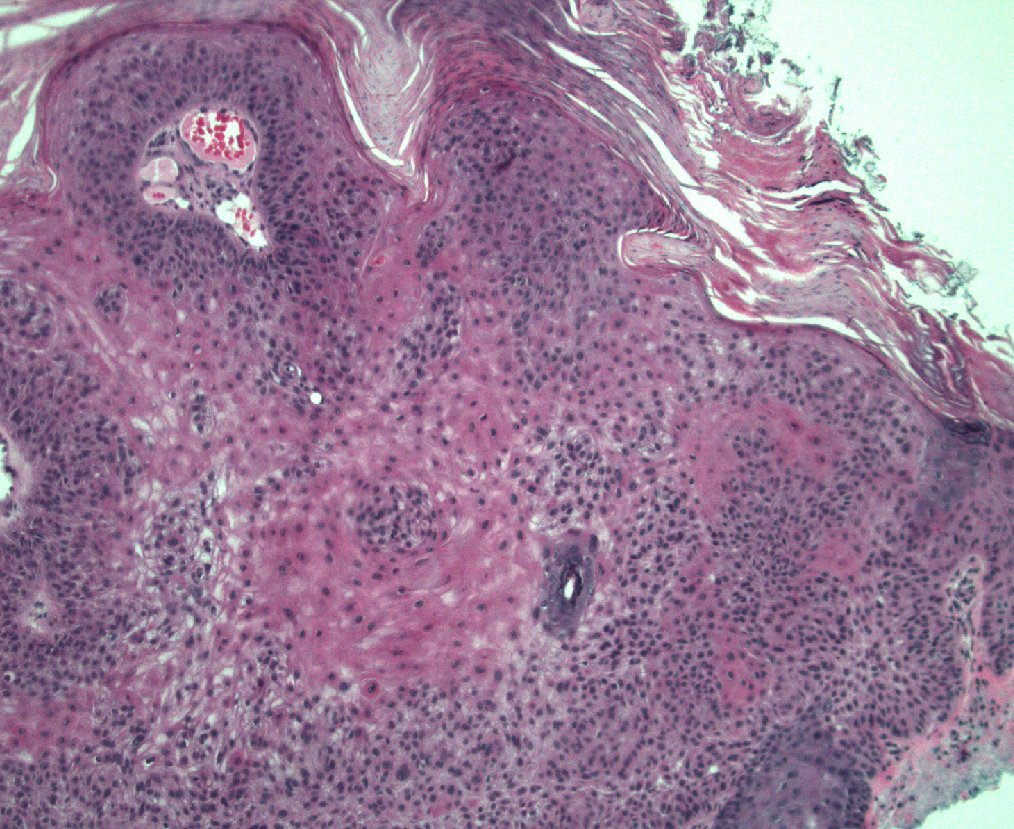

40 F. 10 cm deep thigh mass.

Answer ✅ youtu.be/QDb68_G1HR4?si…

Digital slide 🔬 kikoxp.com/posts/11800.

Differential dx: kikoxp.com/posts/12124

#BSTpath #pathologists #pathology #pathTwitter